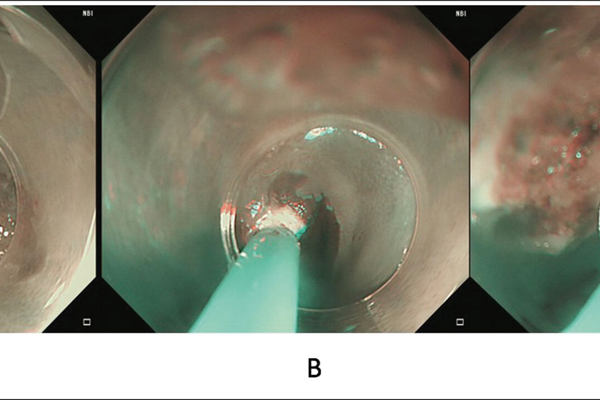

Gastric inlet patch – an under-diagnosed cause of globus